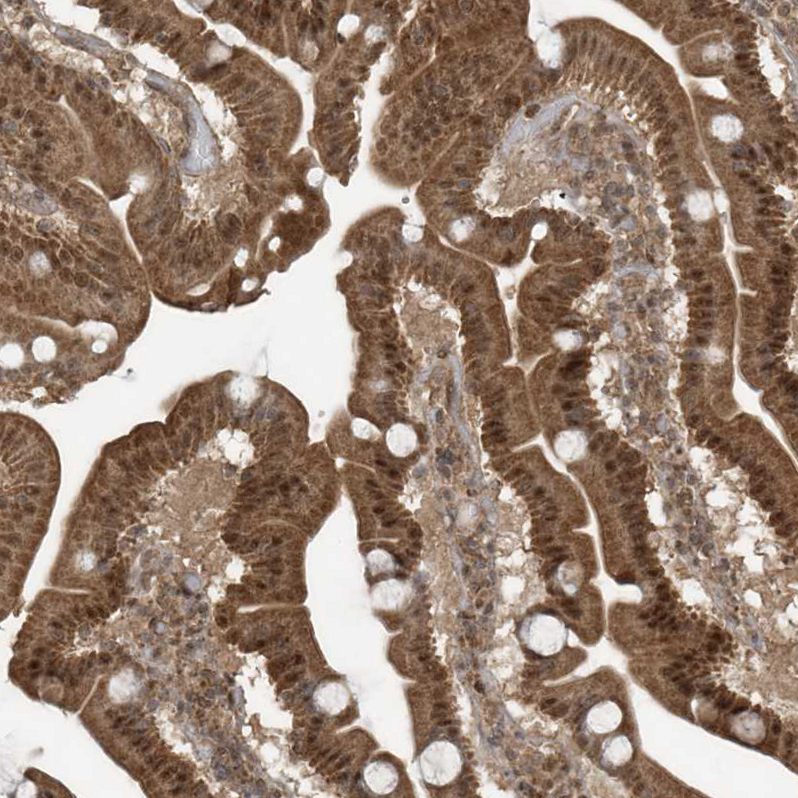

Immunohistochemical staining of human testis shows moderate nuclear positivity in Leydig cells.